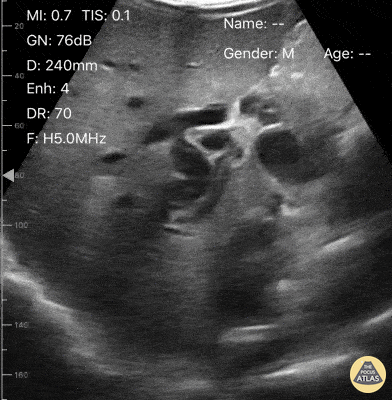

Biliary - Extreme GB distention in setting of cholangiocarcinoma

A 40-year-old male presented to the ED with several week hx unintentional weight loss and new onset jaundice. POCUS of his RUQ demonstrated an overtly distended gallbladder with plethoric intra-hepatic circulation causing compression of the right kidney. As expected, he had laboratory evidence of an elevated direct bili and acute kidney injury. Subsequent MRI confirmed the diagnosis of cholangiocarcinoma. Dr. Victor Bang. Emergency Physician at Hospital das Clínicas de Marília. Co-founder of Pocus Jedi. @vmjbang